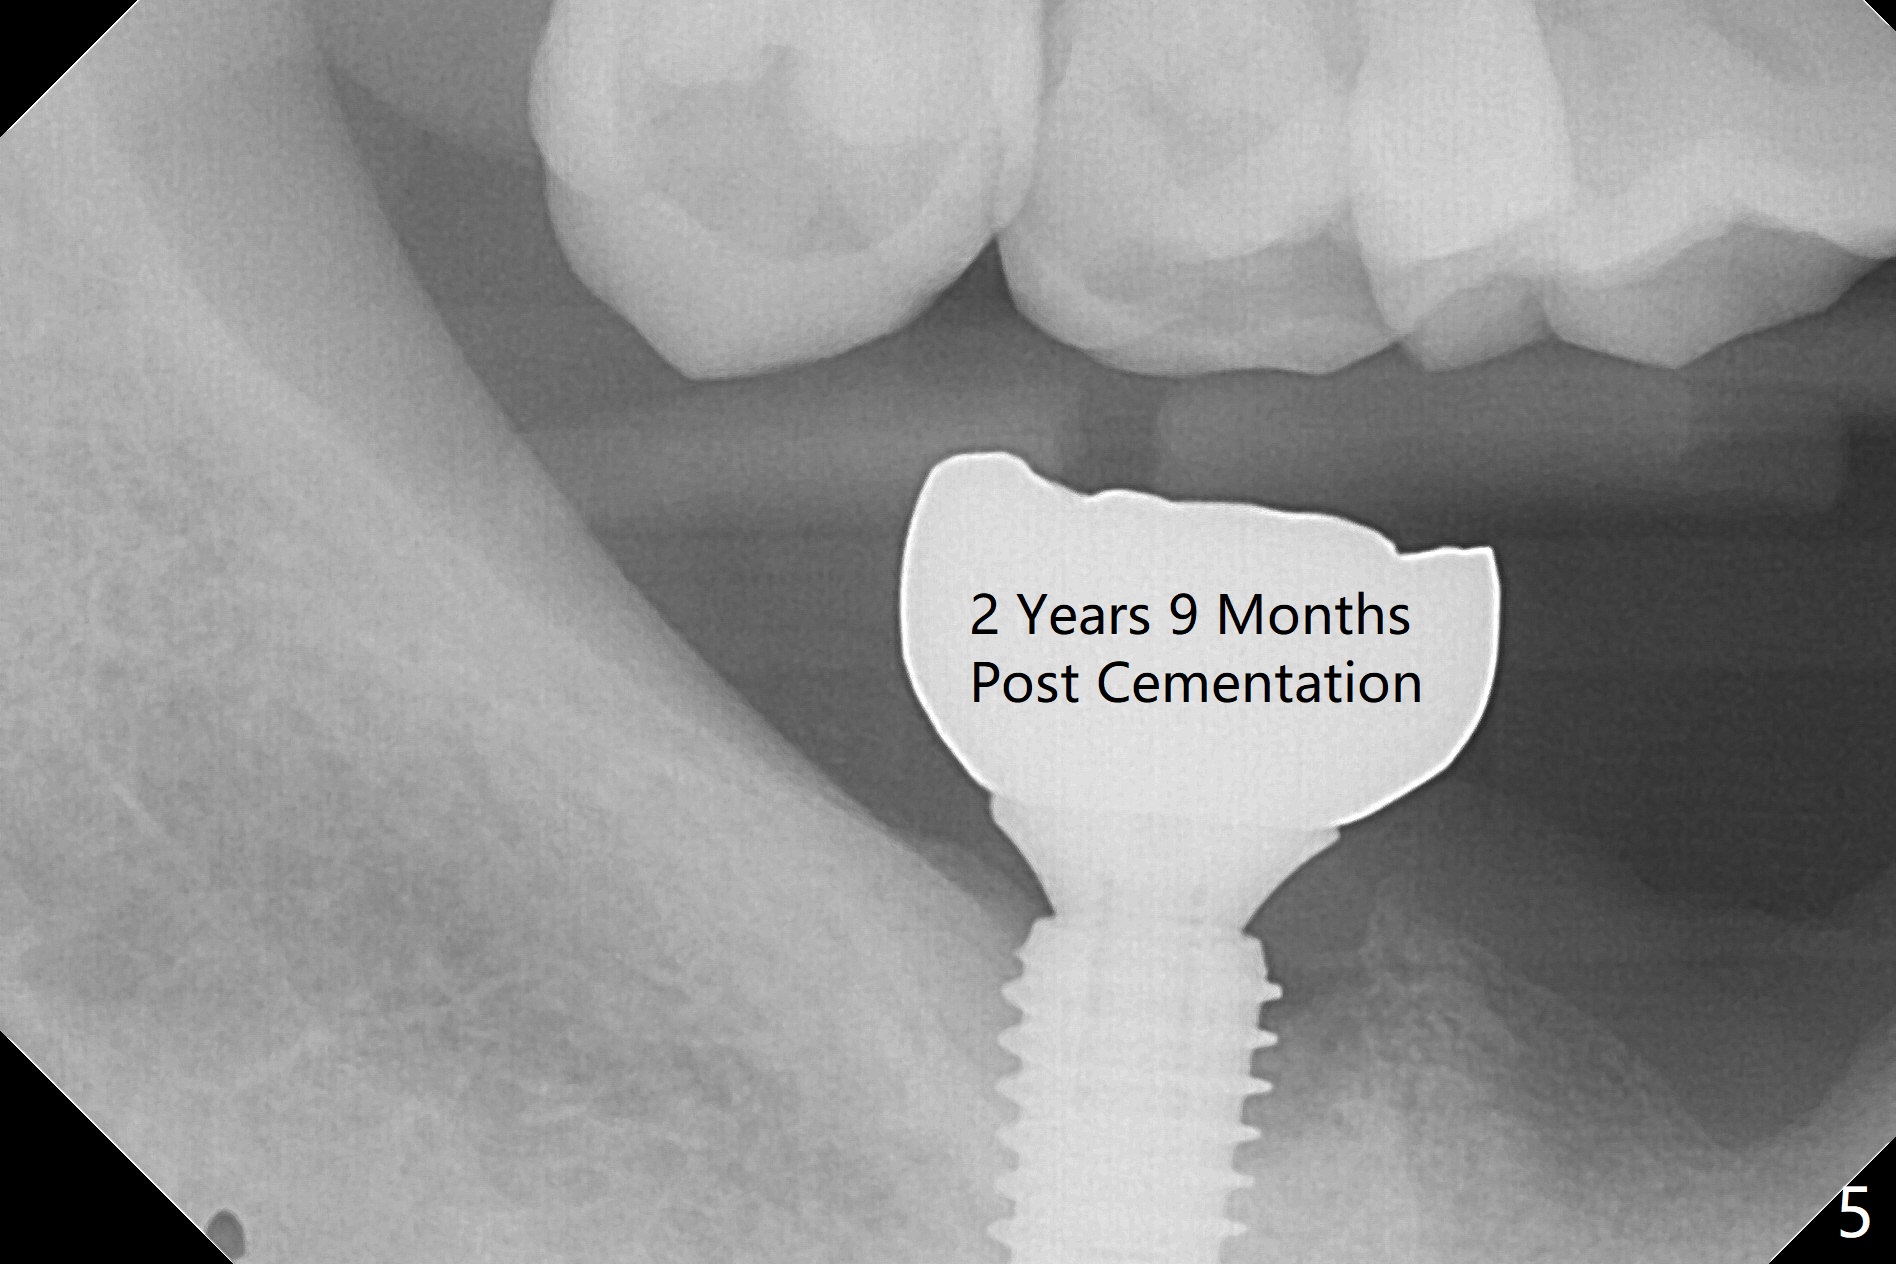

The leukoplakia at the sites of #31 and 32 is most likely related to smoking and the supraerupted teeth #1 and 2 (Fig.0 ^). After osteotomy for 11.5 mm at #31 (Fig.1), it appears that the bone height is not as much as expected. The last two drills for sequential osteotomy are 4.3x13 and 4.8x11.5 mm. A 5x11.5 mm UF implant is placed slightly subcrestal with insertion torque > 50 Ncm (Fig.2). Following placement of 6.5x2 mm healing abutment, the opposing tooth needs adjustment for height. Orthodontic intrusion of the opposing tooth is scheduled 2 days later. It is accidental to find root fracture of the mesial root of the tooth #30 (Fig.1 <). There is minimal bone resorption coronally 5 months postop (Fig.3). A provisional is fabricated at #31 to assist in intrusion of the tooth #2. A crown is cemented 11.5 months postop (Fig.4); the leukoplakia at #31 seems to lessen. The tooth #30 is lost during the pandemic, followed by looseness of the crown and abutment at #31. When the complex is reseated, the occlusal scheme is changed, suggesting incomplete seat of the abutment earlier (Fig.5).